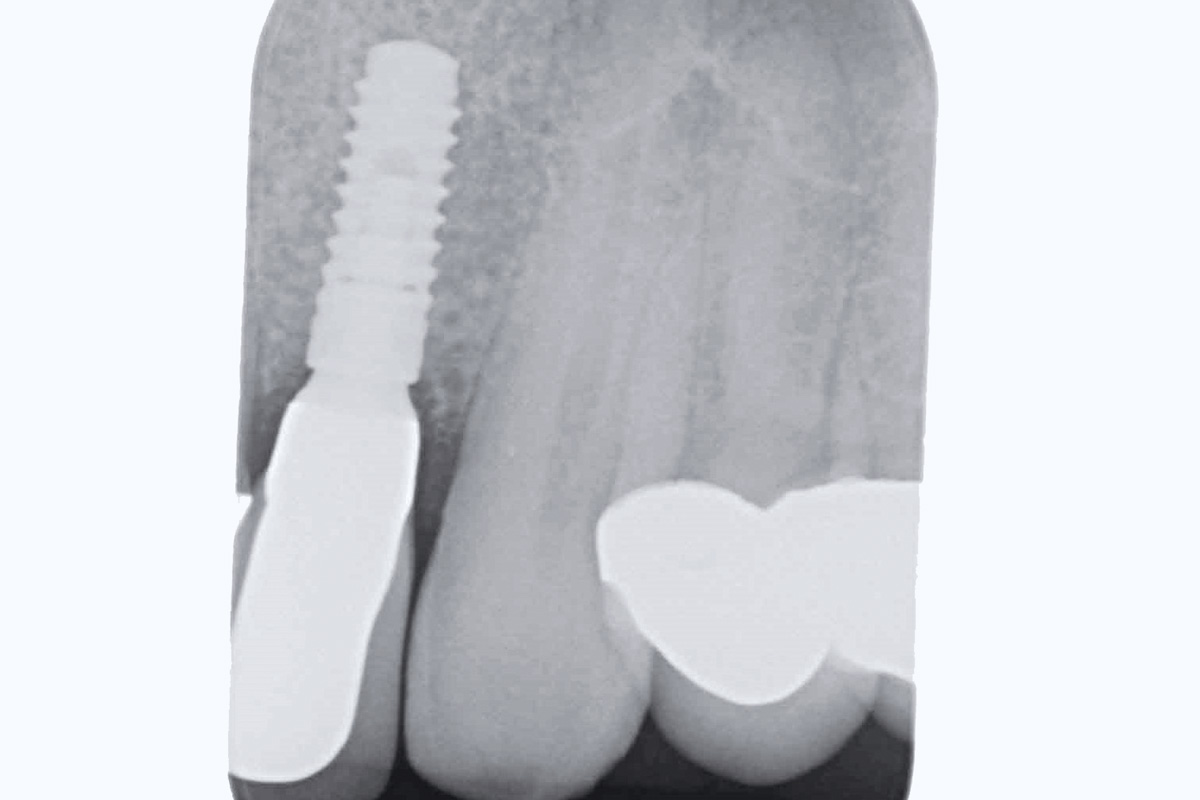

11/19 - Post-op x-ray shows good seating of implantBone augementation with maxresorb® - Dr. R. Cutts

18/19 - X-ray at final restorationBone augementation with maxresorb® - Dr. R. Cutts